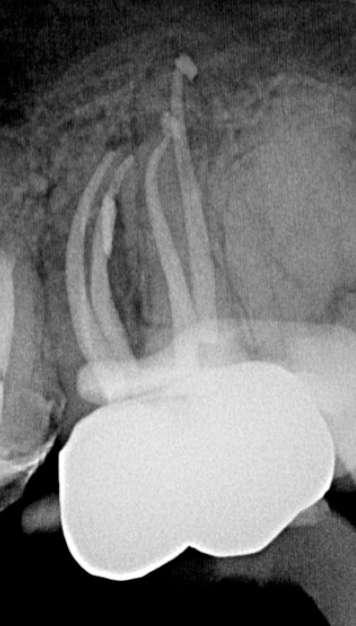

Röntgenologischer Befund:

Das präoperativ angefertigte Röntgenbild (Abbildung 10) zeigt den bereits vom Vorbehandler trepanierten Zahn 27. Die Wurzelfüllung erscheint inhomogen. Das Wurzelfüllmaterial im mesiobukkalen Kanal ist über den röntgenologischen Apex hinaus extendiert und es zeigt sich eine periapikale Osteolyse der mesiobukkalen Wurzel.

Abbildung 10: Präoperative diagnostische Aufnahme